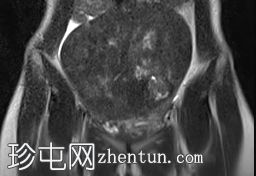

伴有囊性变性的子宫平滑肌瘤

盆腔疼痛,伴有腹部胀满感。

年龄:35岁

性别:女

子宫后壁可见一个边界清晰、体积较大的浆膜下肌瘤,大小约为16.1 x 10.5 x 14.4 cm(宽 x 深 x 高)。

该肌瘤在T1加权像上呈中等信号,在T2加权像上呈低信号,内部区域呈囊性变性。

该肿块导致正常子宫结构严重变形。增强扫描显示轻度不均匀强化,未见弥散受限征象或提示恶性肿瘤的可疑强化。

此外,子宫后壁可见多个小型子宫肌瘤,位于肌壁内和浆膜下,无任何退化征象。

双侧卵巢增大,各有超过10个卵泡,呈珍珠串状排列,周围未见优势卵泡。这些发现符合多囊卵巢的形态学特征。